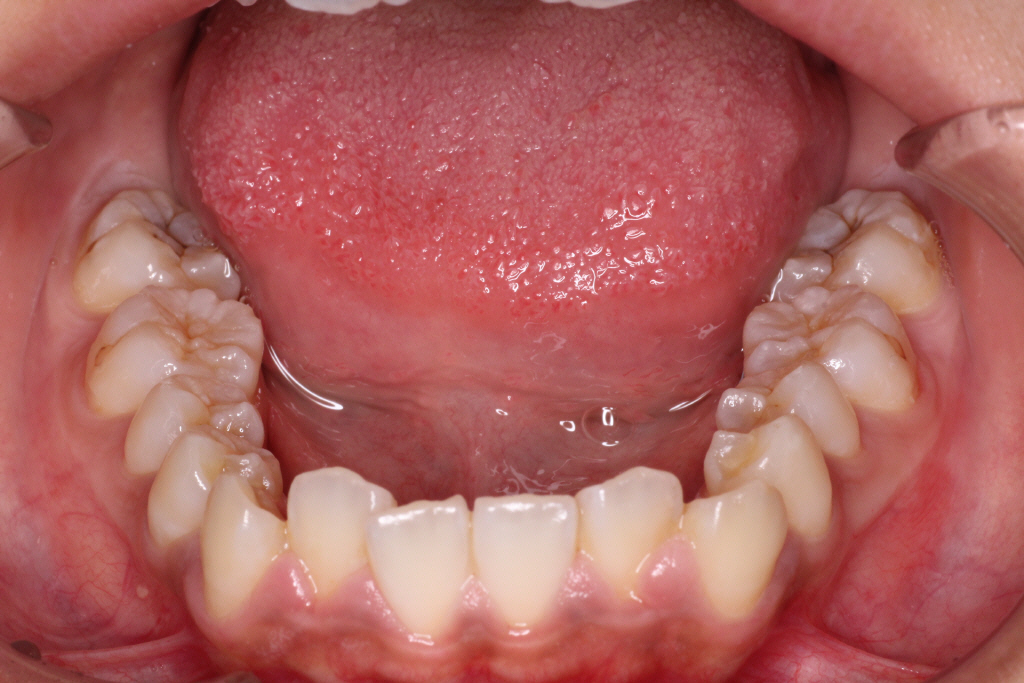

初診時のお口の中の状態です。

上の前から2番目の歯が下の歯列より内側にあり叢生です。

側方の上下の咬合関係が理想の上1本に対して下2本の理想的な噛み合わせではない。

歯列の幅がせまい。